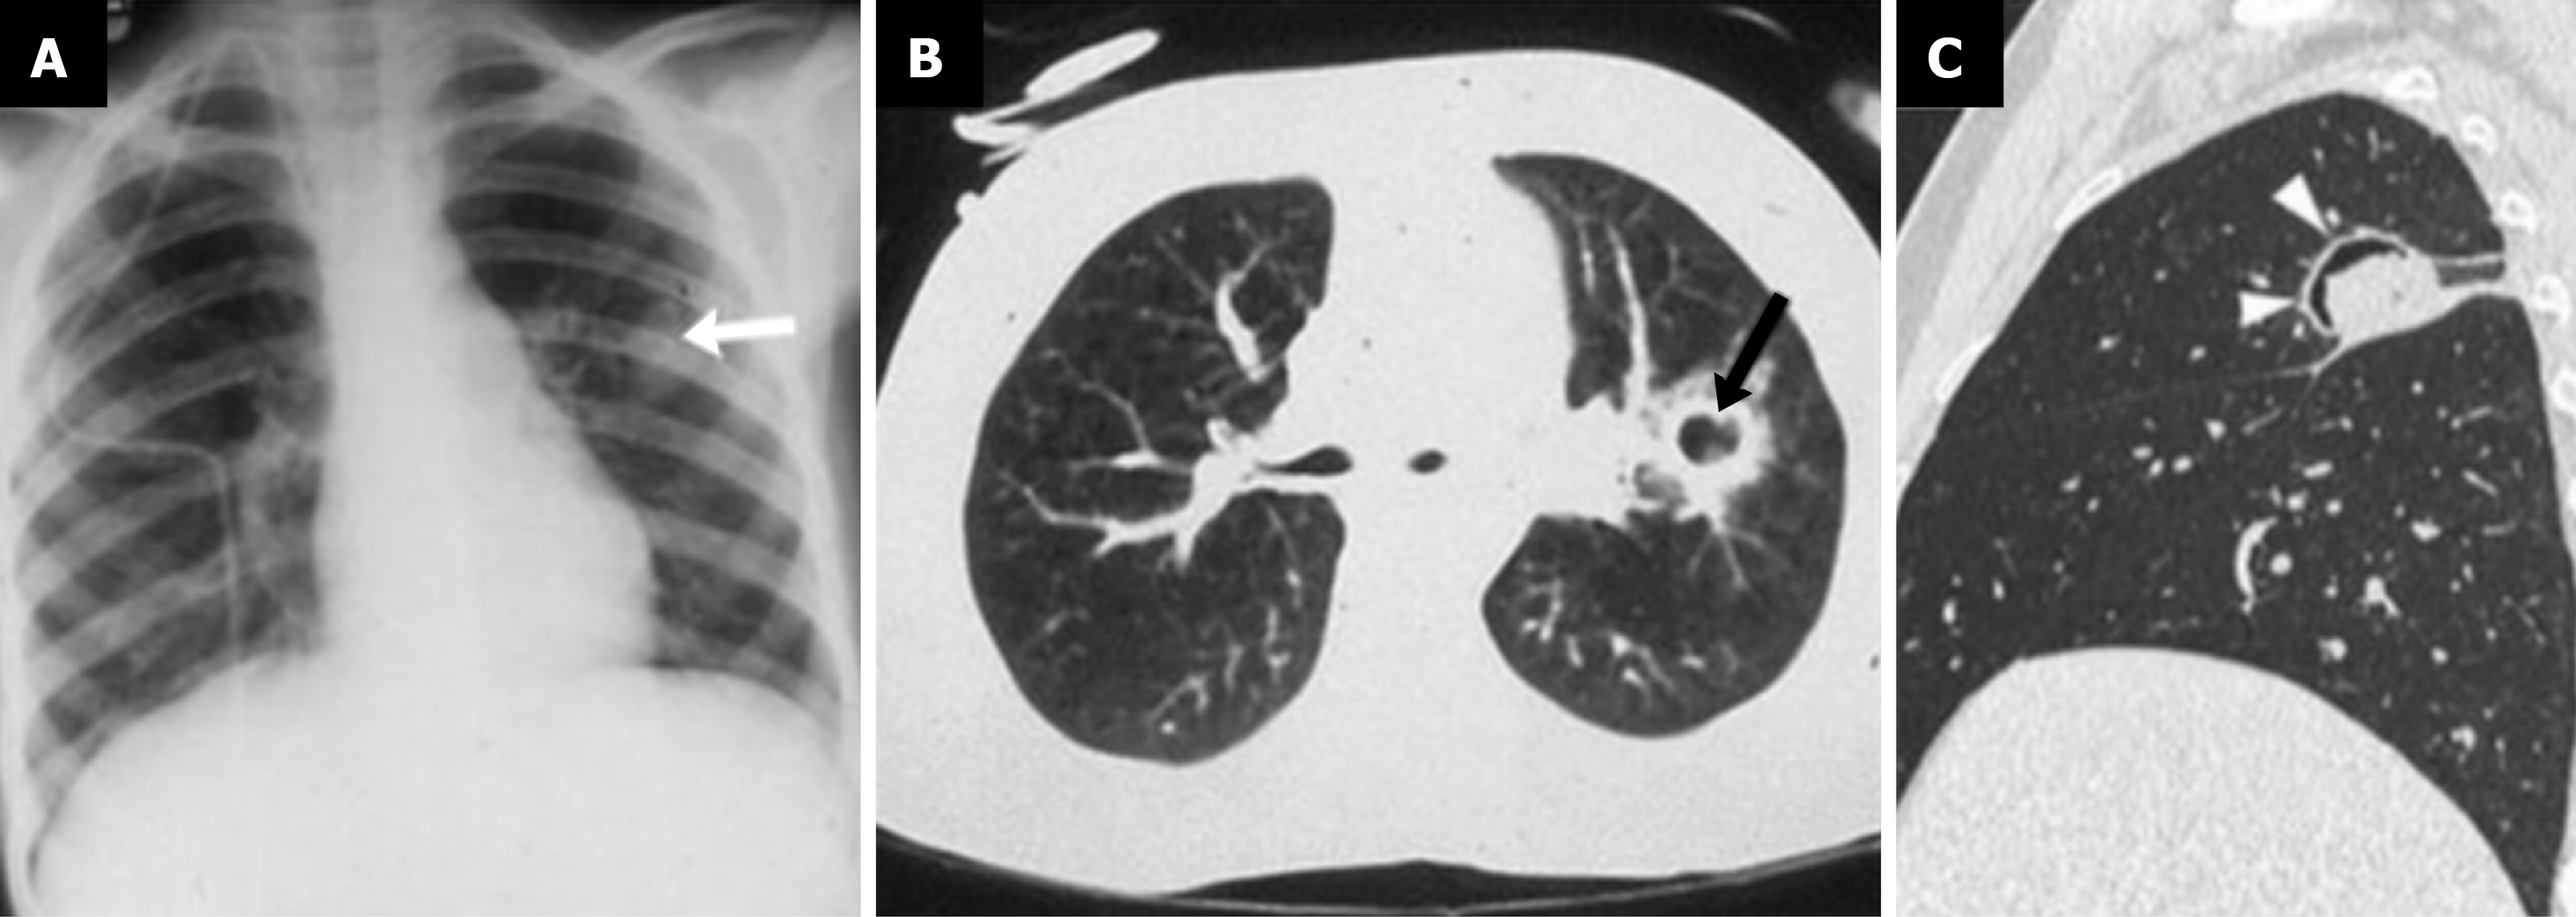

Among fungal pathogens, Aspergillus species are the most frequently implicated. Pulmonary aspergillosis exists along a spectrum, with manifestations dependent on the host’s immune status. In immunocompetent children with pre-existing cavities, colonization by Aspergillus can result in a saprophytic aspergilloma or also known as a “fungus ball”. Radiographically, this appears as a mobile, round mass within a pre-existing cavity, typically surrounded by a crescent-shaped rim of air separating the mass from the cavity wall. This is known as the air-crescent sign (Figure 3) and it can shift depending on the patient’s position[39,40].

Figure 3

Figure 3 Aspergillus infection in a child[7]. A: Chest X-ray showcases a solitary rounded pulmonary lesion in a patient with leukemia (arrow); B: Further evaluation with computed tomography demonstrates cavitation of the lesion and a ground glass halo sign (arrow); C: Different immunocompromised patient with fungal infection showcasing the "air crescent sign" (arrowheads). Citation: Varotto A, Orsatti G, Crimì F, Cecchin D, Toffolutti T, Zucchetta P, Stramare R. Radiological Assessment of Paediatric Fungal Infections: A Pictorial Review With Focus on PET/MRI. In Vivo 2019; 33: 1727-1735. Copyright © 2019 The Author(s). Published by the International Institute of Anticancer Research (https://iv.iiarjournals.org/content/editorial-policies).

Invasive forms of aspergillosis, including angio-invasive and airway-invasive types, primarily affects severely immunocompromised individuals such as transplant recipients or patients with prolonged neutropenia. Angio-invasive disease leads to hemorrhagic infarctions and tissue necrosis, which often appears on imaging as nodules surrounded by ground-glass opacity, known as the “halo sign”. As necrosis progresses, the air-crescent sign may reappear, indicating central cavitation[7,43]. Airway-invasive aspergillosis, which infiltrates the deeper layers of the bronchial wall, may lead to airway, narrowing, obstruction, or rupture, resulting in air-leak phenomena such as pneumomediastinum. CT imaging is essential for detecting these subtle changes and guiding clinical management[44,45].